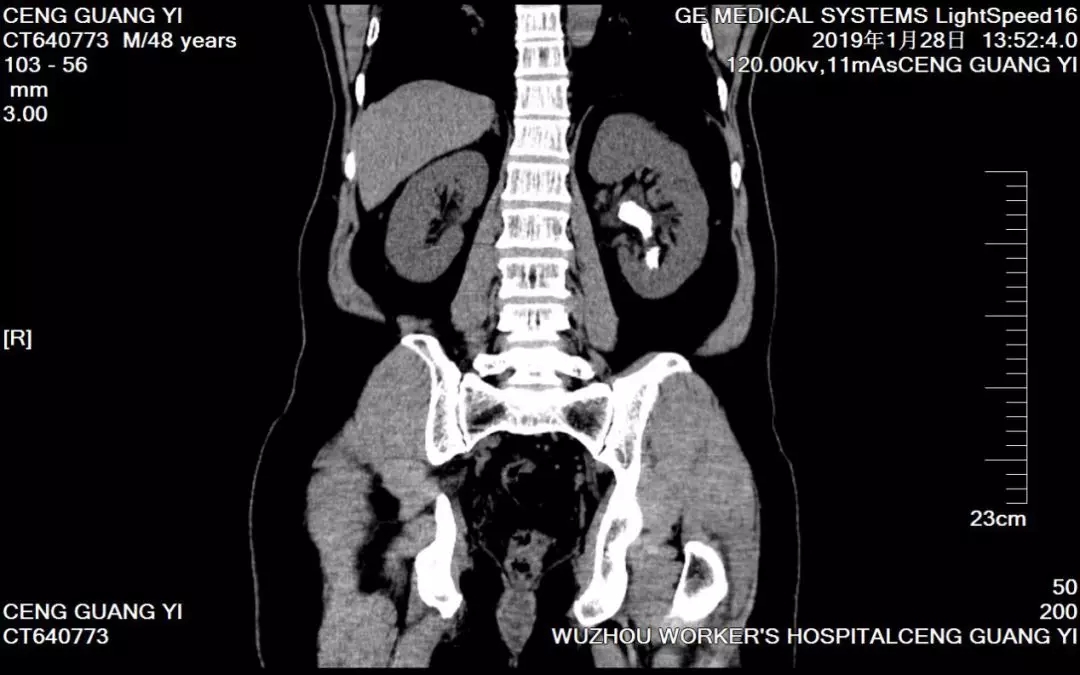

患者曾先生,48岁,因“反复左侧腰痛伴发热血尿半月余”,曾经四处求医,尝试过药物排石及体外震波碎石等治疗方法,但收效甚微。经了解,曾先生前来梧州市工人医院泌尿外科就诊。入院检查后,医生诊断为左肾铸型结石伴感染。

(图为曾先生术前检查CT片)